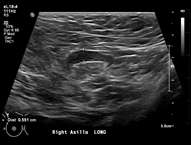

Features concerning for malignancy include round shape, increased cortical thickness and loss of fatty hilum1. The relationship of the lymph node cortex to hilum can be used to classify lymph node morphology and likelihood of malignancy. As the cortical thickness increases, there are reciprocal changes in the hilum beginning with hilar effacement and progressing to absence or replacement of the lymph node hilum2,3. Cortical thickening (figure 3) is considered the earliest morphologic change associated with malignancy; however, this finding is nonspecific with a low positive predictive value1-3. Absent/replaced hilum (figure 4) is the most specific for malignancy with a positive predictive value of 58-97%2.